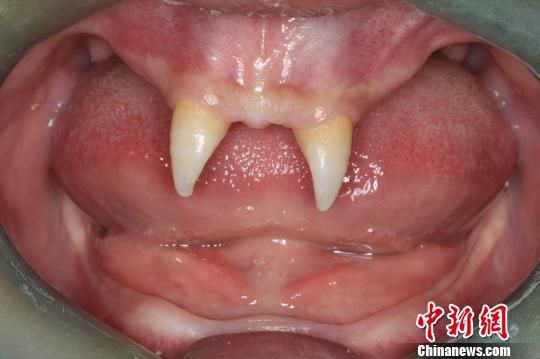

16歲男孩罹患染色體疾病臉上長(zhǎng)獠牙

【byb.cn】?( 來(lái)源:中國(guó)新聞網(wǎng)? )中新網(wǎng)重慶12月18日電 (何雷 韓璐)今年16歲的張成(化名)從生下來(lái)就似乎得了一種怪病,身上毛發(fā)稀少、面部發(fā)育不好。更奇怪的是,別人家的孩子都長(zhǎng)牙吃東西了,而他卻一直沒(méi)有長(zhǎng)出正常的牙齒,只有在上顎部分有兩顆比較突出且對(duì)稱的牙齒,看起來(lái)就像一對(duì)“獠牙”。18日,記者在第三軍醫(yī)大學(xué)西南醫(yī)院見(jiàn)到了張成及他的母親王慧。

16歲的張成一直沒(méi)有長(zhǎng)出正常的牙齒,只有在上顎部分有兩顆比較突出且對(duì)稱的牙齒,看起來(lái)就像一對(duì)“獠牙”?!∥髂厢t(yī)院口腔科供圖 攝